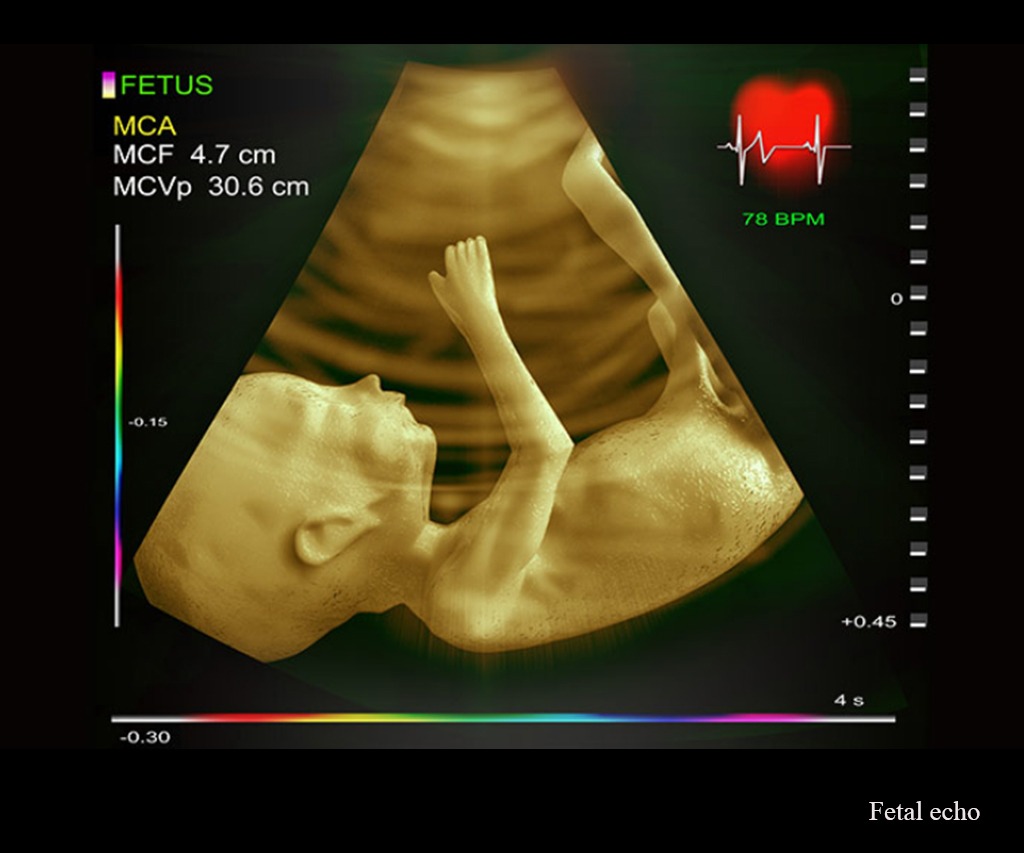

Our Obstetrics & Gynecology department is very well equipped with modern labour ward, ultrasonography, phototherapy room with incubator, warmer, CTG, CRYO, Colposcopy, Operation Theater equipped with Laparoscopic & hysteroscopic equipment.

A Gynecology and Obstetrics (OB-GYN) Department is a hospital or clinic division focused on womens reproductive health, covering pregnancy, childbirth, postpartum care (Obstetrics) and the diagnosis, treatment of diseases, and general wellness of the female reproductive system (Gynecology), including menopause, fertility, contraception, and cancers.